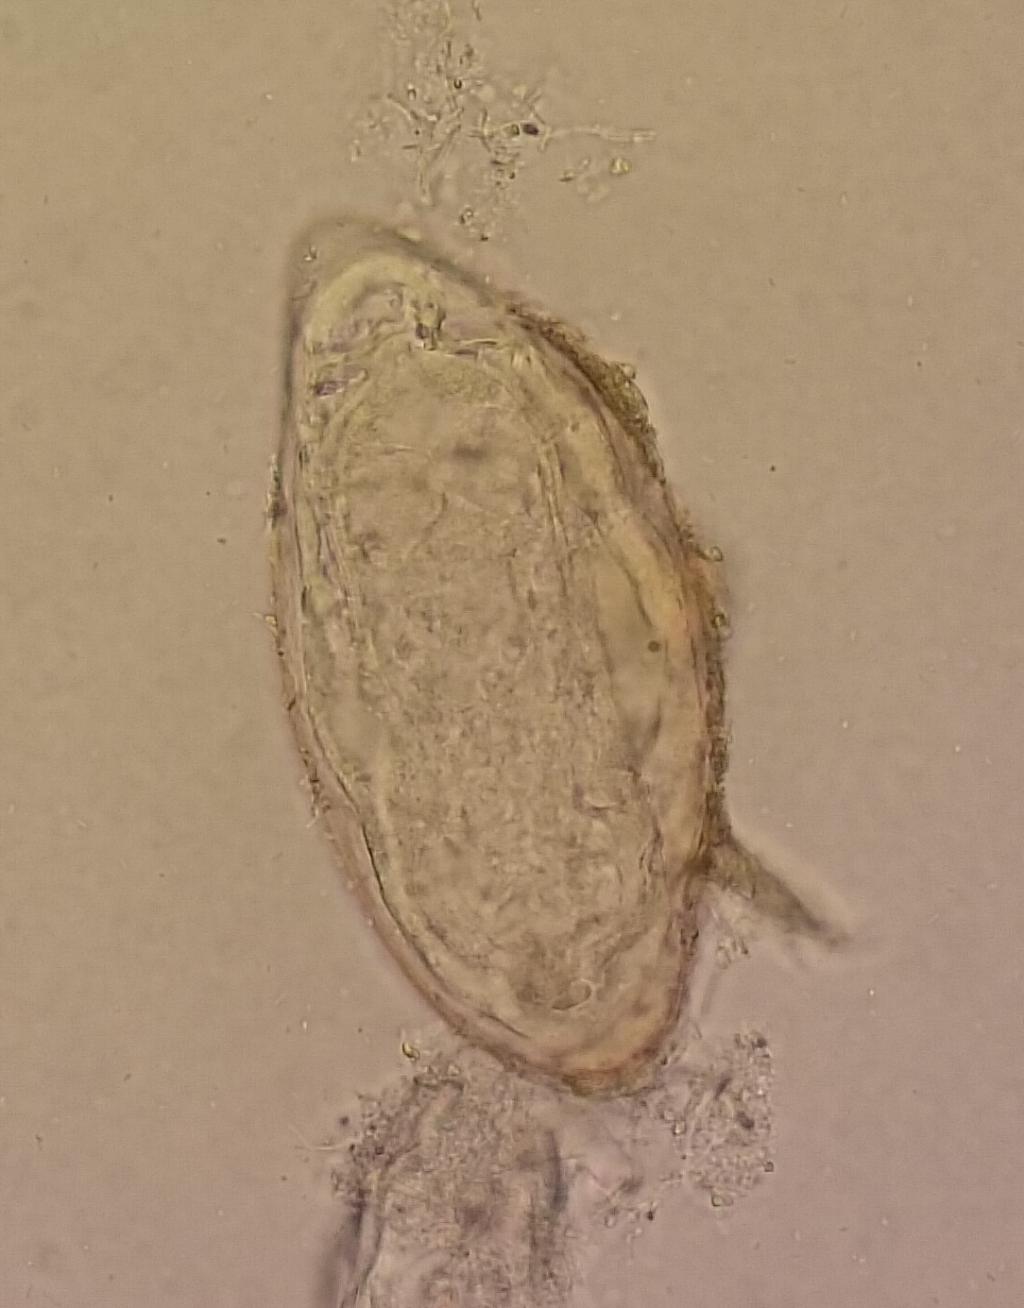

Een 17-jarige man, afkomstig uit Eritrea en sinds drie weken in Nederland, heeft sinds een week rugpijn en progressieve uitval van beide benen. Bij lichamelijk onderzoek is er een parese van beide benen, een urineresidu na mictie en een verminderde tastzin vanaf de navel. Hij heeft geen koorts. Bloedonderzoek laat een eosinofilie zien, waarna fecesonderzoek wordt verricht. Welke parasiet wordt daarin aangetroffen?